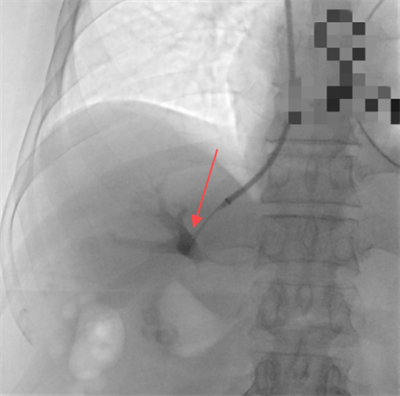

随后,赵扬程介入手术团队决定为患者施行经颈静脉肝内门体分流术(TIPS),术中经颈静脉入路精准植入8毫米覆膜支架,于肝静脉与门静脉间构建分流通道,同步完成食管胃底曲张静脉栓塞。术后门静脉压力由36厘米水柱降至20厘米水柱,出血立即停止,血红蛋白水平稳定回升。该手术在有效降低血管压力的同时维持肝脏血流灌注,为患者争取到后续治疗的宝贵时间窗。

图一:肝穿刺针成功进入肝门静脉